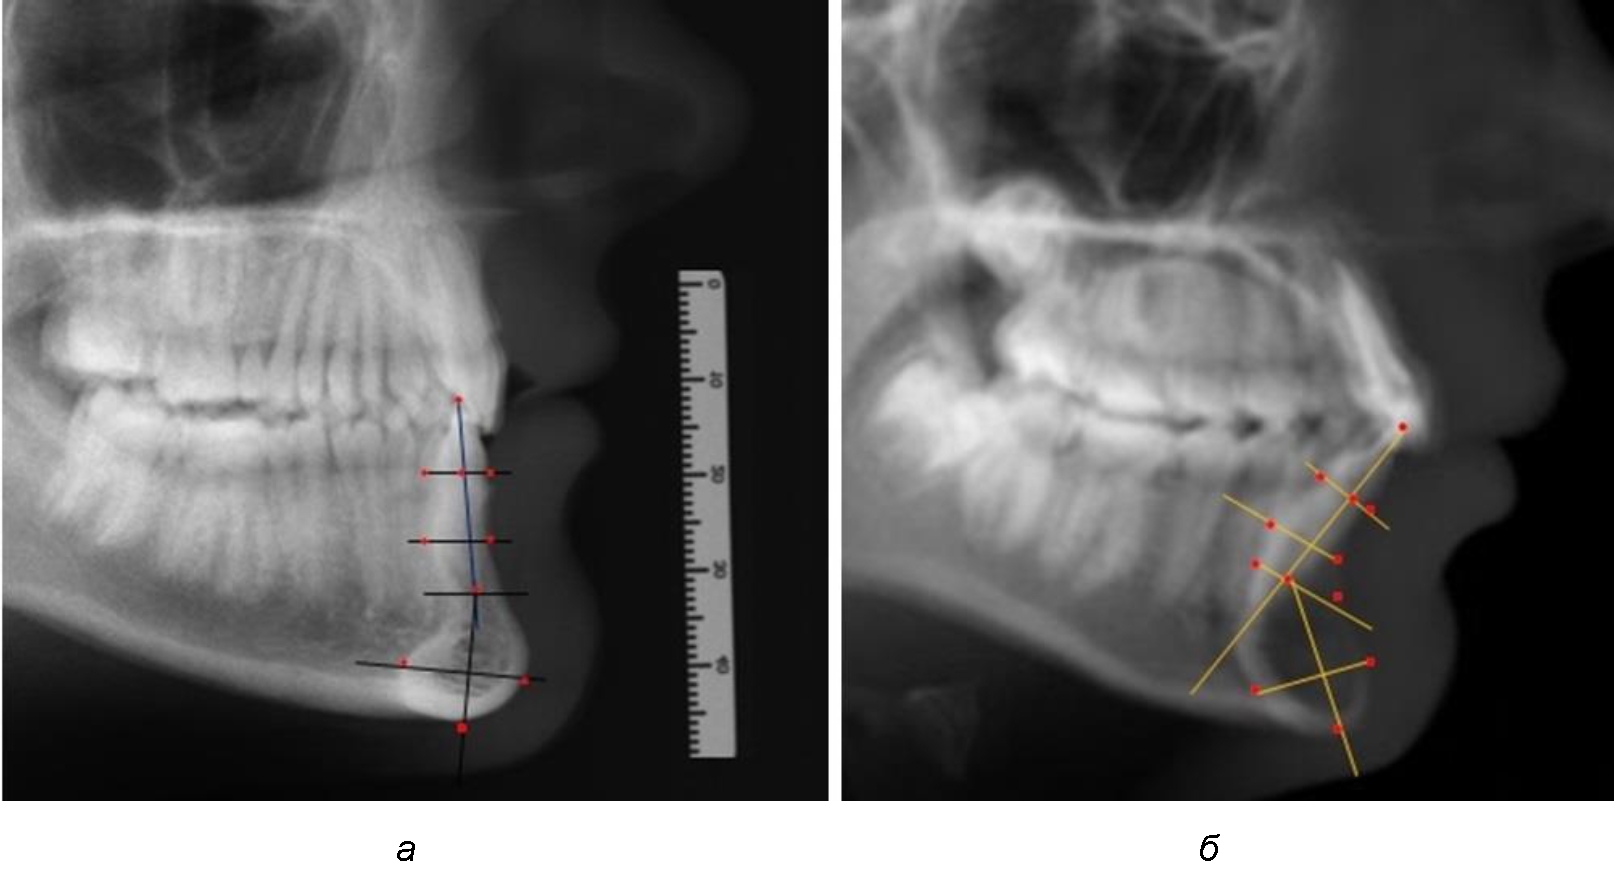

При анализе полученных данных обращает на себя внимание факт того, что из вертикальных параметров зубоальвеолярной части сегмента наиболее вариабельным является размер между апикальными точками Downs и Schwarz (BSM–B), который составлял (6,79 ± 0,54) мм, при величине сигмального отклонения – 2,35. Также большая ошибка репрезентативности и сигмальное отклонение было отмечено при оценки ширины подбородочного выступа. В связи с этим встречались варианты резцовых сегментов нижней челюсти различные как по ширине, так и по высоте, а также по расхождению положения апикальных точек по Downs и Schwarz (рис. 3).

Варианты резцовых сегментов нижней челюсти различные как по ширине, так и по высоте, а также по расхождению положения апикальных точек по Downs и Schwarz представлены на рис. 4.

Рис. 4. Особенности нижнечелюстного резцового сегмента на ТРГ у людей при среднем (а), широком (б) и узком (в) вариантах

При аномалиях окклюзии в сагиттальном направлении и характерных для них различных вариантах протрузионного и/или ретрузионного патологического положения передних зубов, как правило, сопровождается изменениями параметров подбородочного выступа. Учитывая многообразие форм аномалий окклюзии, параметры подбородочного выступа вариабельны как по сагиттали, так и по трансверсали.

Нередко отмечается деформация подбородочного выступа и различное его положение по отношению к зубоальвеолярной части сегмента. При мезиальной окклюзии нередко нижняя подбородочная точка смещается кзади по отношению к условной срединной вертикали нижнего резца, а при дистальной окклюзии отмечается компенсаторное отклонение подбородка кпереди (рис. 5).

Рис. 5. Особенности нижнечелюстного резцового сегмента на ТРГ у людей при мезиальной (а) и дистальной (б) окклюзии

Кроме того, так же как и у людей с физиологической окклюзией, определялось различие в положении апикальных точек Downs и Schwarz, что, по нашему мнению, может определять тактику лечения патологических форм протрузии/ретрузии резцов с учетом биотипа костной ткани.